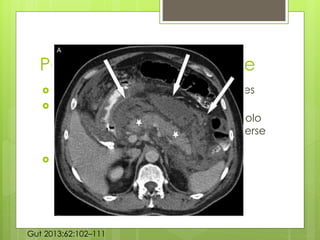

Pancreatitis edematosa

 Aumento difuso del páncreas debido al

edema inflamatorio. T

 TAC, parenquima pancreático muestra el

realce homogéneo, y la grasa

peripancreatica por lo general muestra

algunos cambios inflamatorios de

densidad.

 Puede haber algún fluido.

Gut 2013;62:102–111

Pancreatitis Necrotizante

 Se desarrolla en 5-10% de los pacientes

 Implica al páncreas y los tejidos

peripancreaticos, poco común que solo

afecte a los tejidos y menos común verse

afectado el parénquima.

 Resultado de la mala perfusión